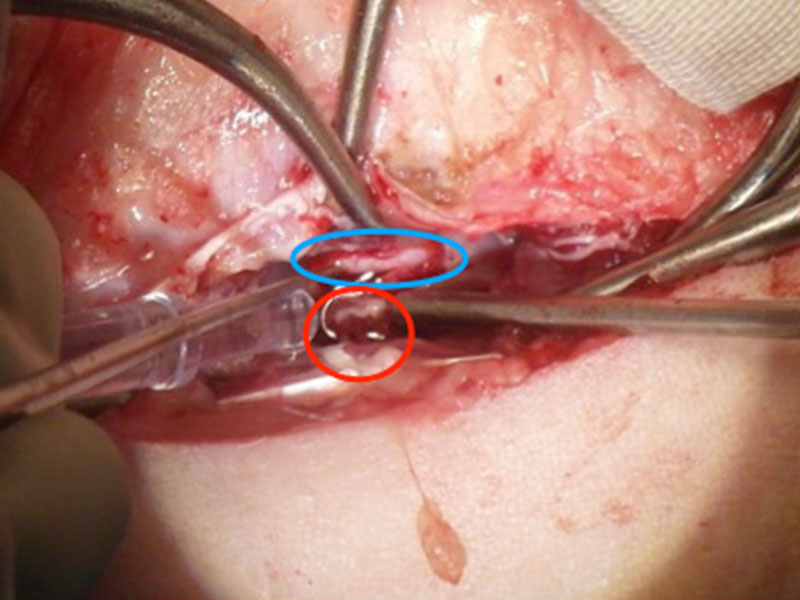

經過電腦斷層掃描(CT)後,發現在胸腰椎交界處的脊髓受到脫出的椎間盤物質壓迫,應為造成小胖後肢突然無法站立的主因,於是盡快安排手術將脫出物質取出,降低脊髓壓力。

在手術中可見白色的壓迫物(紅圈處)以及淡粉紅色的脊隨(藍圈處) 。